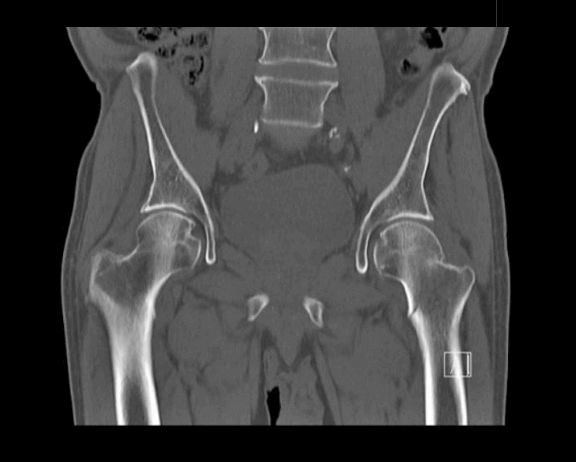

КТ тазобедренных суставов проводится исключительно по направлению специалиста. Показания для проведения данного вида КТ: травматические поражения костей таза, тазобедренных суставов или новообразования указанных участков.